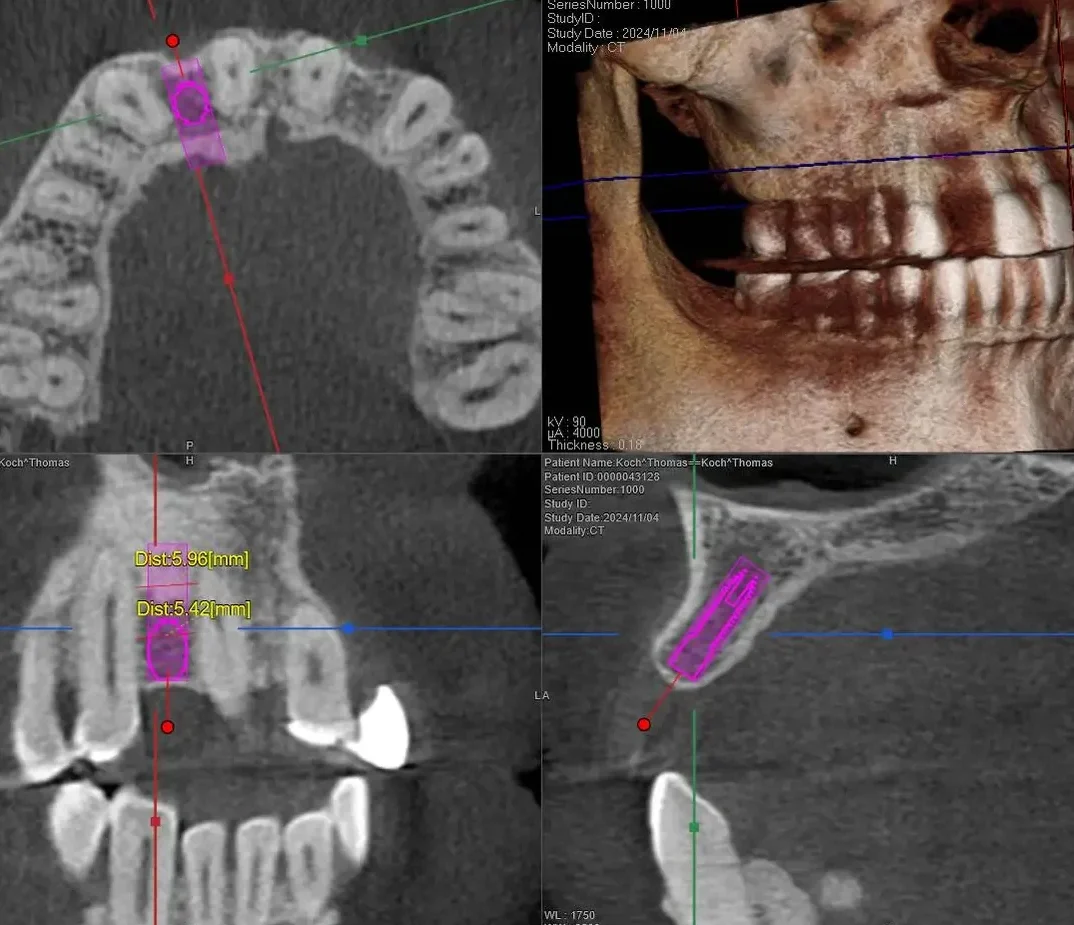

A 3D scan was taken to measure the bone. Although a bit limited in space for an implant, there was enough space to place an implant if done very precisely.

A narrow implant was Placed by Dr. Peter Mann.